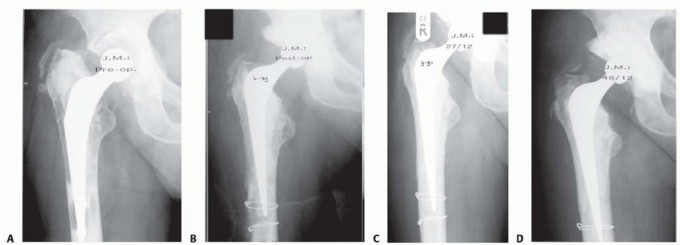

DEFINITION Proximal femur replacement is a salvage limb-sparing surgery for nononcologic and oncologic indica…